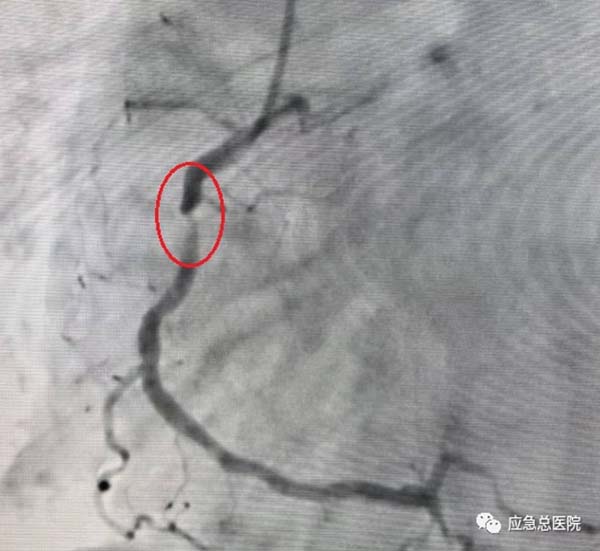

介入手术前

考虑到患者基础病多,病情复杂,治疗棘手,经过综合分析研判后,导管室范煜东主任率团队为患者实施手术。

曹大夫与患者留影

40分钟后,成功为患者植入两枚冠脉支架,迅速开通了冠脉循环,挽救了患者的心肌,为其康复后顺利出院奠定了坚实的基础。其精湛的医术、认真负责的精神、及时的救治,让患者和家人由衷称赞。于是便出现了文中开头的一幕。